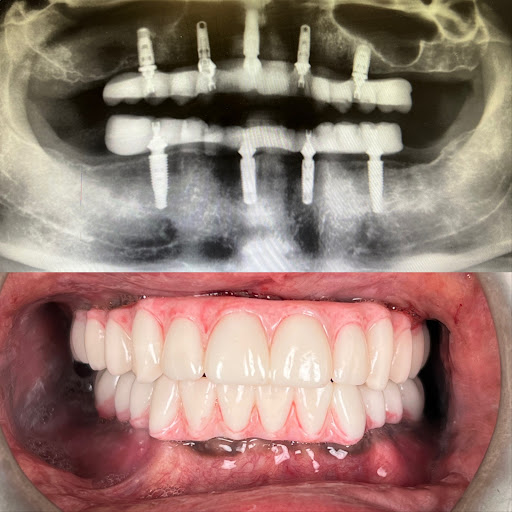

Photos